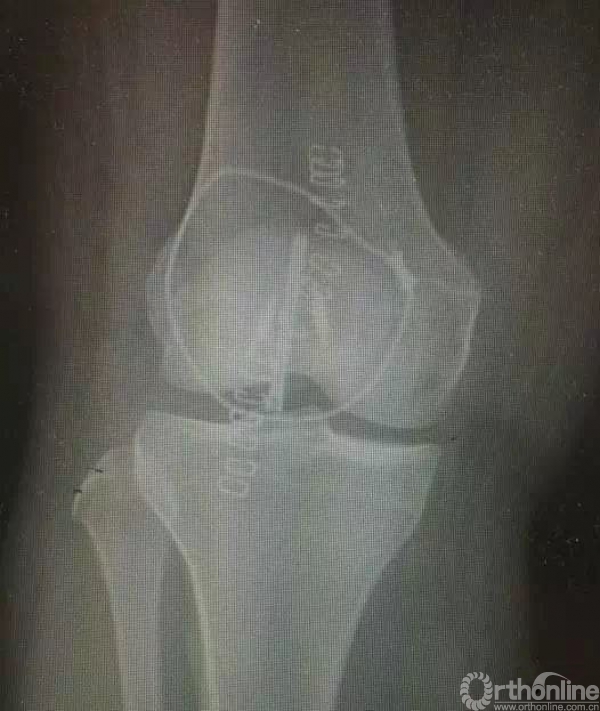

2.这例患者是否骨折?——该例病例为二分髌骨,并非髌骨骨折,发生率为8%,多数位于上外侧。

术前X线,下级粉碎,中下段上下分层。